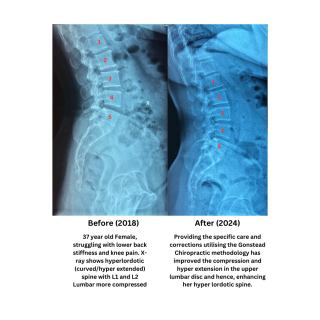

Hyperlordosis (Hyperextension) of Lumbar Spine